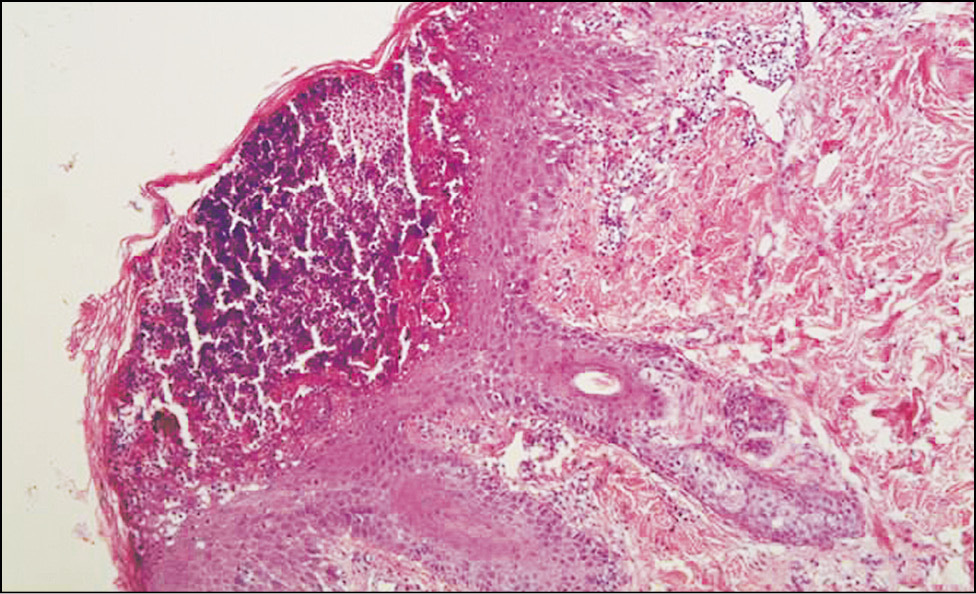

Pic. 2. The same patient. Histological picture of Barber's pustular psoriasis.

The preparation subcorneally determines the spongioform pustule of Kagoi. Against the background of acanthosis, there are separate granulocytic neutrophil infiltrates. Stained with hematoxylin-eosin ×100.